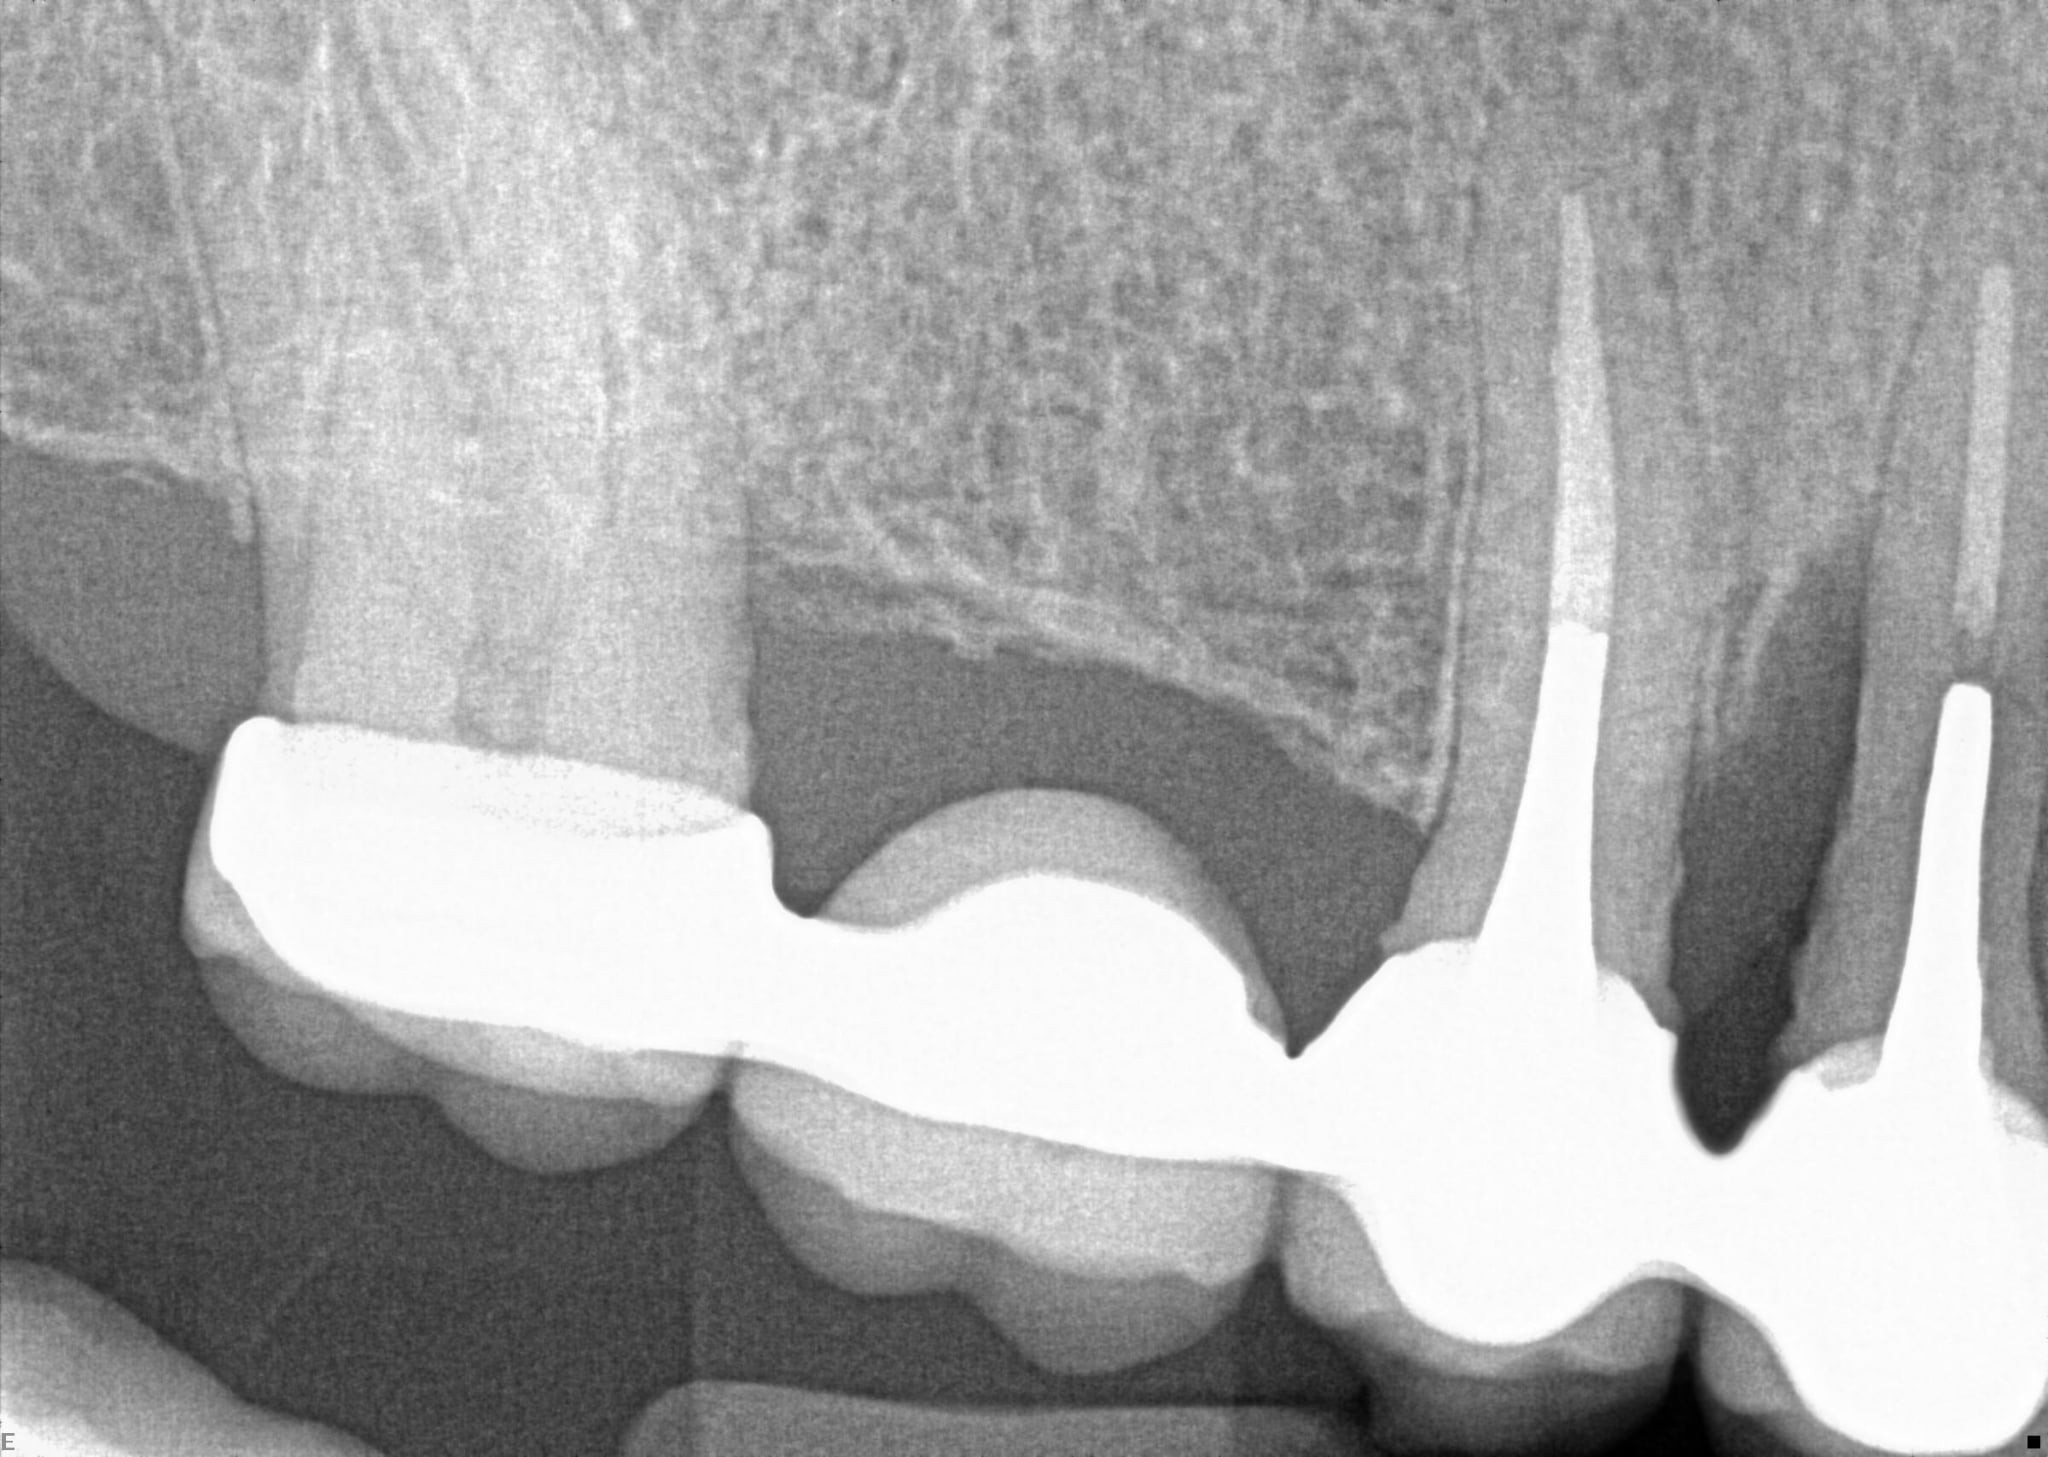

2. What option can describe the post placement in the X ray bellow for the tooth # 4.6?